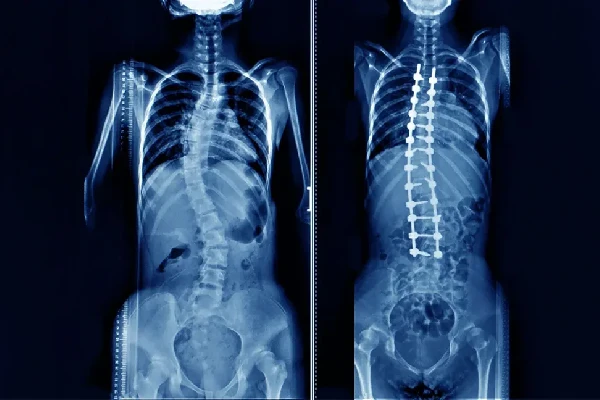

مقایسه تصاویر قبل و بعد از عمل